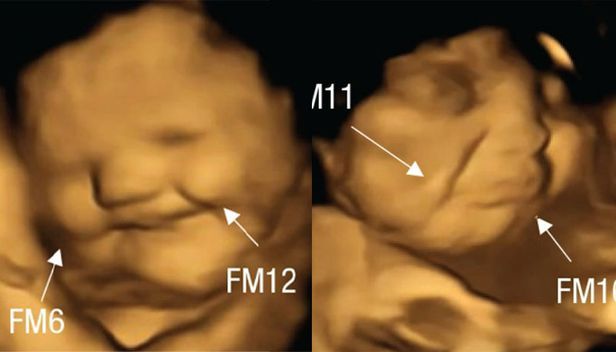

당근을 섭취한 임신부 집단의 태아들에게서는 미소 짓는 듯 올라간 입꼬리, 케일을 섭취한 집단의 태아들에게선 울상을 한 모습이 관찰됐다. 사진은 자료사진.

임신부가 캡슐을 섭취한 뒤 20분가량 이후 태아의 표정에는 변화가 생기기 시작했다. 4D 초음파로 스캔한 결과, 당근을 섭취한 집단의 태아들에게선 입꼬리가 올라가는 등 웃는 얼굴이 확인됐다.

케일을 섭취한 임신부 집단의 태아들은 얼굴을 찡그리거나 입술을 꾹 다무는 등 울상이 된 표정을 지었다.